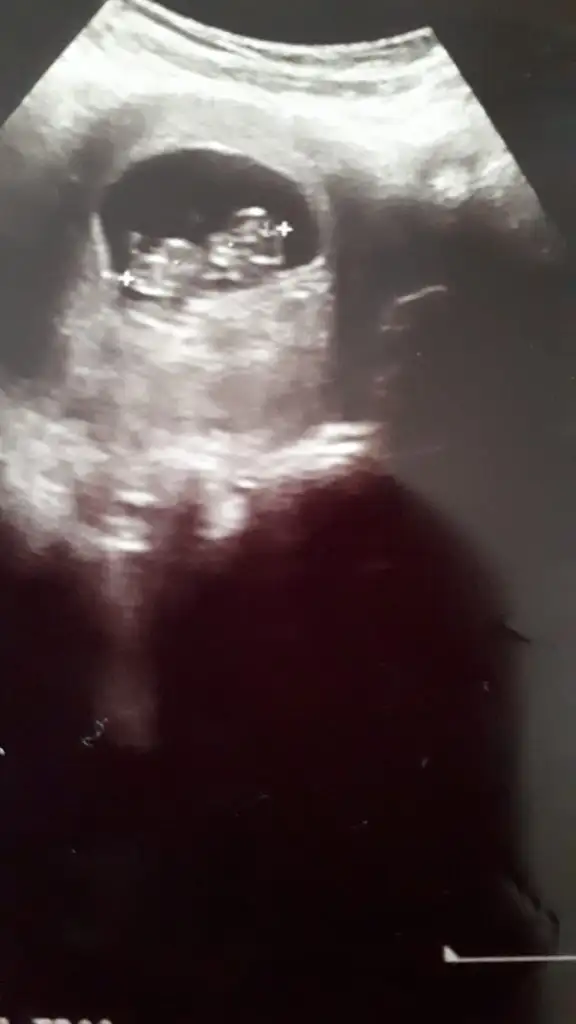

Kaç haftalık 6 7 olmalı erkek keseye göreKese konumundan bakabilir misiniz rica etsem

7 haftalık ay hadi inşallah teori doğru tutar iki kızım var teşekkür ederimKaç haftalık 6 7 olmalı erkek keseye göre

KIz olabilirKizlar cinsiyet tahmininde bulunabilir misiniz :) dr bisey demedidaha